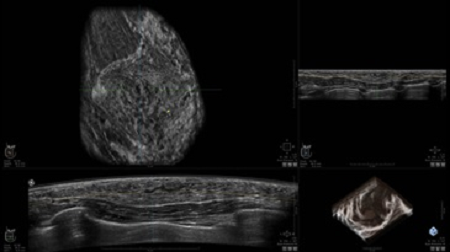

• Получение объемных 3D изображений с возможностью покадрового просмотра

• Получение изображений в поперечной плоскости (в реальном времени) и в коронарной плоскости (статическая, для указания нахождения соска)

• Встроенный сверхширокий вогнутый датчик C15-6XW: диапазон частот: 4 - 15 МГц; длина апертуры: 15,3 см; длина сканируемого участка: 16,9 см; количество элементов: 768

• Глубина сканирования до 5 см.

• Получение одного объемного изображения менее чем за 60 секунд

• Отображение объемных 3D ультразвуковых изображений, которые состоят из традиционных поперечных и воссозданных коронарных и сагиттальных проекций

• Стандартизованная ориентация изображения: «толстый срез» в коронарной плоскости; поперечная; сагиттальная плоскость; радиальный и антирадиальный поворот изображения; просмотр исключительно области интереса

• Изменяемая толщина среза: 0,5 - 10,0 мм (шаг 0,5 мм)

• Срез: 0,5 - 2,0 мм (шаг 0,5 мм)